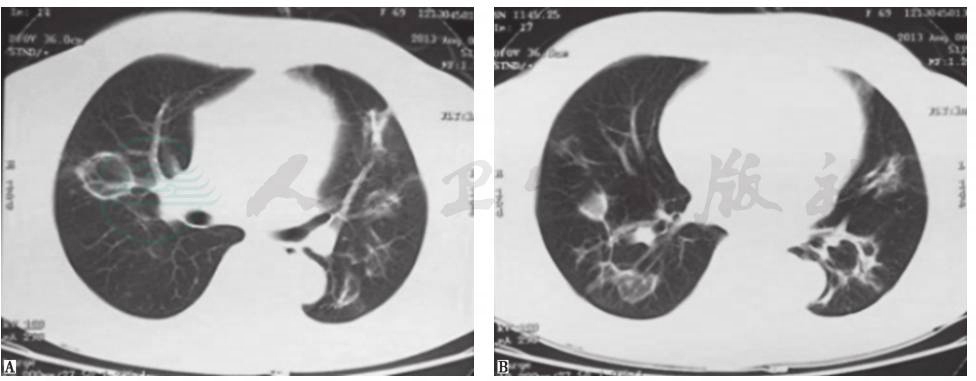

肉芽肿性多血管炎(GPA):既往称为韦格纳肉芽肿,是一种坏死性肉芽肿性血管炎,属于自身免疫性疾病。该病主要侵犯上、下呼吸道和肾脏,通常以鼻黏膜和肺组织的局灶性肉芽肿性炎症为开始,继而进展为血管的弥漫性坏死性肉芽肿性炎症。临床常表现为鼻和鼻旁窦炎、肺病变和进行性肾衰竭,还可累及关节、眼、皮肤、心脏、神经系统及耳等。侵犯肺部时影像学表现可有多样性、多发性及多变性等特点(图6)。本例患者虽有蛋白尿的肾脏损害表现,但临床病程及症状与GPA相距甚远,故考虑GPA可能性不大。

图6 韦格纳肉芽肿胸部CT表现

女性患者,21岁,间断咳嗽2个月,诊断为韦格纳肉芽肿。胸部CT可见双肺多发结节影伴空洞形成,各结节影与血管关系密切